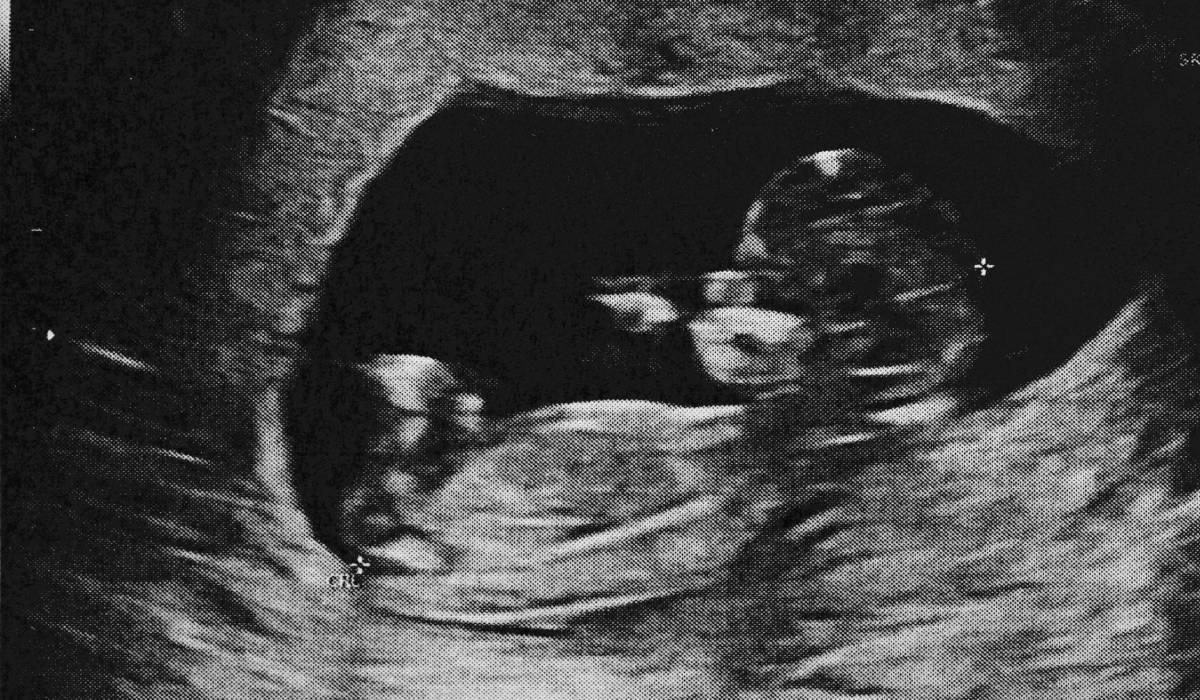

Datorită progreselor în îngrijirea prenatală și în tehnologia imagistică, descoperirea unui lithopedion este astăzi extrem de rară. Medicul poate detecta o sarcină ectopică prin teste repetate de sânge pentru nivelurile hormonului B-HCG și prin investigații cu ultrasunete. Dacă se identifică o sarcină extrauterină, aceasta poate fi tratată fie medicamentos cu metotrexat, fie chirurgical, evitând astfel complicațiile pe termen lung. Dr. Lee subliniază importanța respectării tuturor consultațiilor și investigațiilor atunci când testul de sarcină este pozitiv, pentru a asigura diagnosticul și tratamentul corect.